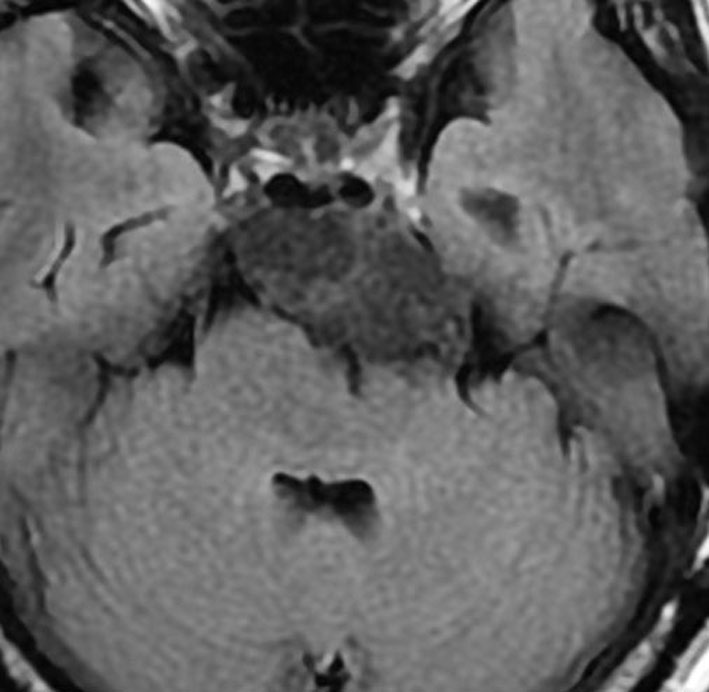

斜台の脊索腫 classical type

CTでは,斜台から左蝶形骨にかけて不規則な骨破壊像がみられます。

MRI T2強調画像(左)では等信号から高信号のまだらな境界が不明瞭な腫瘍が斜台から左海綿静脈洞内に浸潤しているのがみられます。T1強調ガドリニウム増強では,腫瘍がまだらに増強されています。トルコ鞍から鞍上部に伸び,視交差を侵し第3脳室底まで伸展しています。脊索腫が硬膜内に浸潤して神経組織と癒着することは珍しいことではありません。